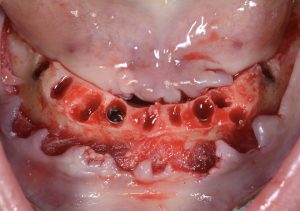

FIG 6